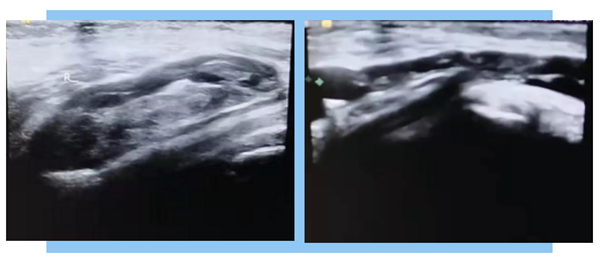

患者肌肉骨骼超聲檢查

經(jīng)檢查提示:患者右膝關(guān)節(jié)腘窩處腓腸肌內(nèi)側(cè)頭-半膜肌腱滑囊可見片狀液性暗區(qū),范圍約63×10×23mm3,內(nèi)可見光帶分隔,CDFI:未見明顯血流信號(hào)。右膝關(guān)節(jié)腘窩囊腫破裂(血腫機(jī)化可能);右膝關(guān)節(jié)多處滑膜增生較厚約16mm,內(nèi)部回聲不均,CDFI:內(nèi)示血流信號(hào)。右膝股四頭肌腱、髕腱未見腫脹及撕裂。